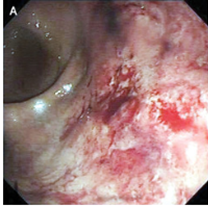

51歳男性。 約36週にわたる黒色皮膚病変の悪化、また6か月にわたる体重減少と腹痛を主訴に皮膚科を受診した。 受診時、身体所見では腹壁に巨大な腫瘤を認め、腋窩、…